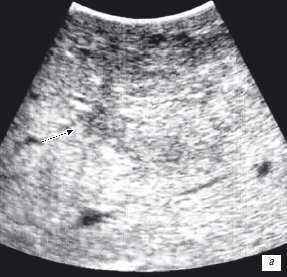

Особенностью проведения интраоперационного ультразвукового исследования у пациентов с первичным поражением печени является то, что гепатоцеллюлярный рак часто развивается на фоне цирроза печени. Следовательно, если опухоль локализуется в толще паренхимы, а так же имеет не большие размеры, пальпаторно определить ее границы крайне затруднительно. Таким образом, задачи установленные перед интраоперационной ультразвуковой томографией были несколько иными, а именно: определение границ опухоли, разметка зоны резекции, определение связи с магистральными сосудами (рис. 2 а,б).

Рис. 2. Метастатические очаги (стрелки) в печени на фоне цирроза.